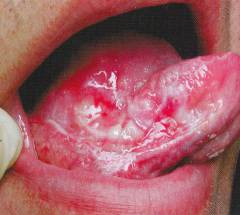

Эрозивно-язвенная

Это тяжелая форма заболевания, трудно поддающаяся терапии. Она в основном затрагивает слизистые оболочки, чаще полость рта, реже — головку полового члена или преддверие влагалища.

На слизистых образуются дефекты, быстро превращающиеся в остро болезненные язвы и эрозии неправильной или округлой формы.

Вокруг этих образований или на удаленных участках кожи наблюдаются характерные высыпания, присущие красному плоскому лишаю.

Язвы и эрозии имеют розовато-бархатистое дно, иногда покрыты пленками или налетами, при удалении которых может возникнуть легкое кровотечение.